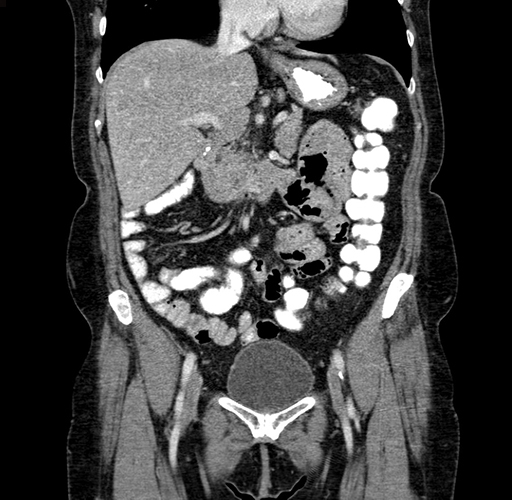

Pre-Chemo: Coronal Venous